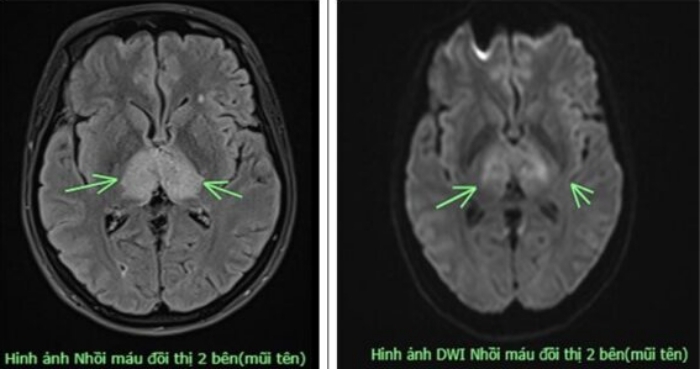

Đau đầu suốt 4 ngày không khỏi, người phụ nữ tự uống thuốc cũng không thuyên giảm, đi khám bất ngờ phát hiện mắc thể đột quỵ hiếm.